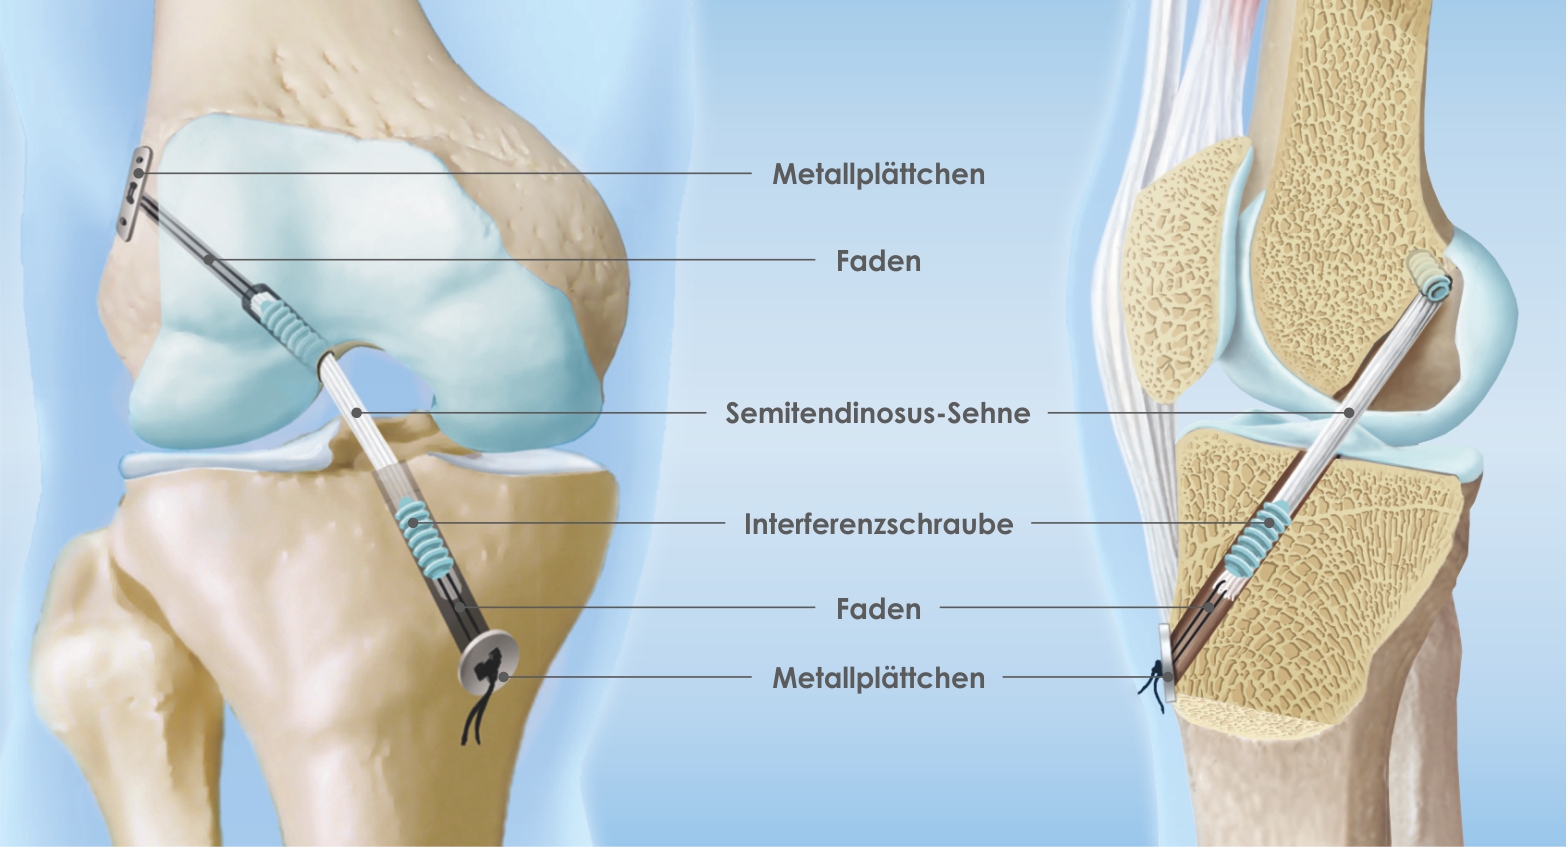

Die Rekonstruktion des VKB wird arthroskopisch assistiert durchgeführt (VKB-Re-konstruktion). Das bedeutet, dass ausser der Transplantatentnahme alle Schritte mit Hilfe des Arthroskops im Gelenkinneren stattfinden. Als Transplantat wird meist eine Beugesehne (Semitendinosus-Sehne, alternativ Quadriceps- oder Patellarsehne) entnommen. Über Bohrkanäle, die in Ober- und Unterschenkelknochen gesetzt werden – ebenfalls arthroskopisch assistiert –, wird das Transplantat eingezogen und mit speziell für diese Operation entwickelten Schrauben (Interferenzschrauben) fixiert. Die Schrauben bestehen in der Regel aus einer abbaubaren Zuckerverbindung und müssen daher nicht entfernt werden.